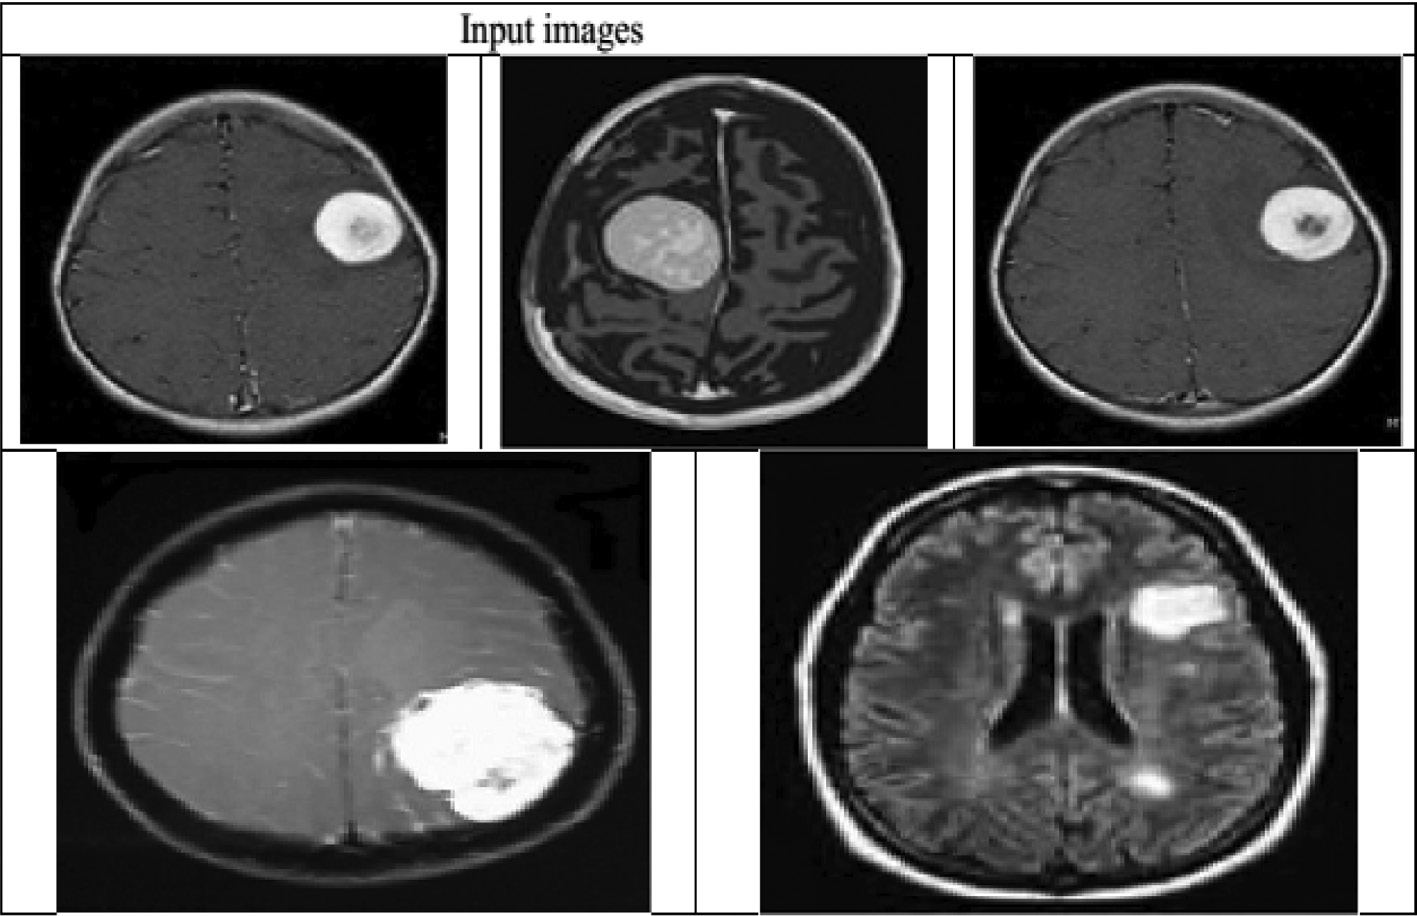

With the help of this RG procedure, the input images are segmented. The segmented image output is shown in Figure 1.

Figure 1: Segmentation Output.(A) Input image. (B) Segmented tumor part.

(A) Input image. (B) Segmented tumor part.

Experimental Approach to Input Image.

In this proposed watermarking, we hybridize lossless data compression and encryption techniques to embed EHR and image hash in medical images. The hybrid approach increases the security of the information (Table 3). Here, at first, we segment the ROI part from the image using the RG algorithm. Then, we encrypt the ROI part using SHA-256 and encrypt the EHR using the ECC algorithm. Thereafter, we concatenate the information and then compress it using the AC algorithm. The compressed bit stream is embedded into the medical image. Finally, we obtain the watermarked image. We used medical images of size 256×256. Figure 6 shows the original and watermarked images, and Figure 7 shows the experimental results of segmentation.

Figure 6: Experimental Output.(A) Input image. (B) Watermarked image.

(A) Input image. (B) Watermarked image.